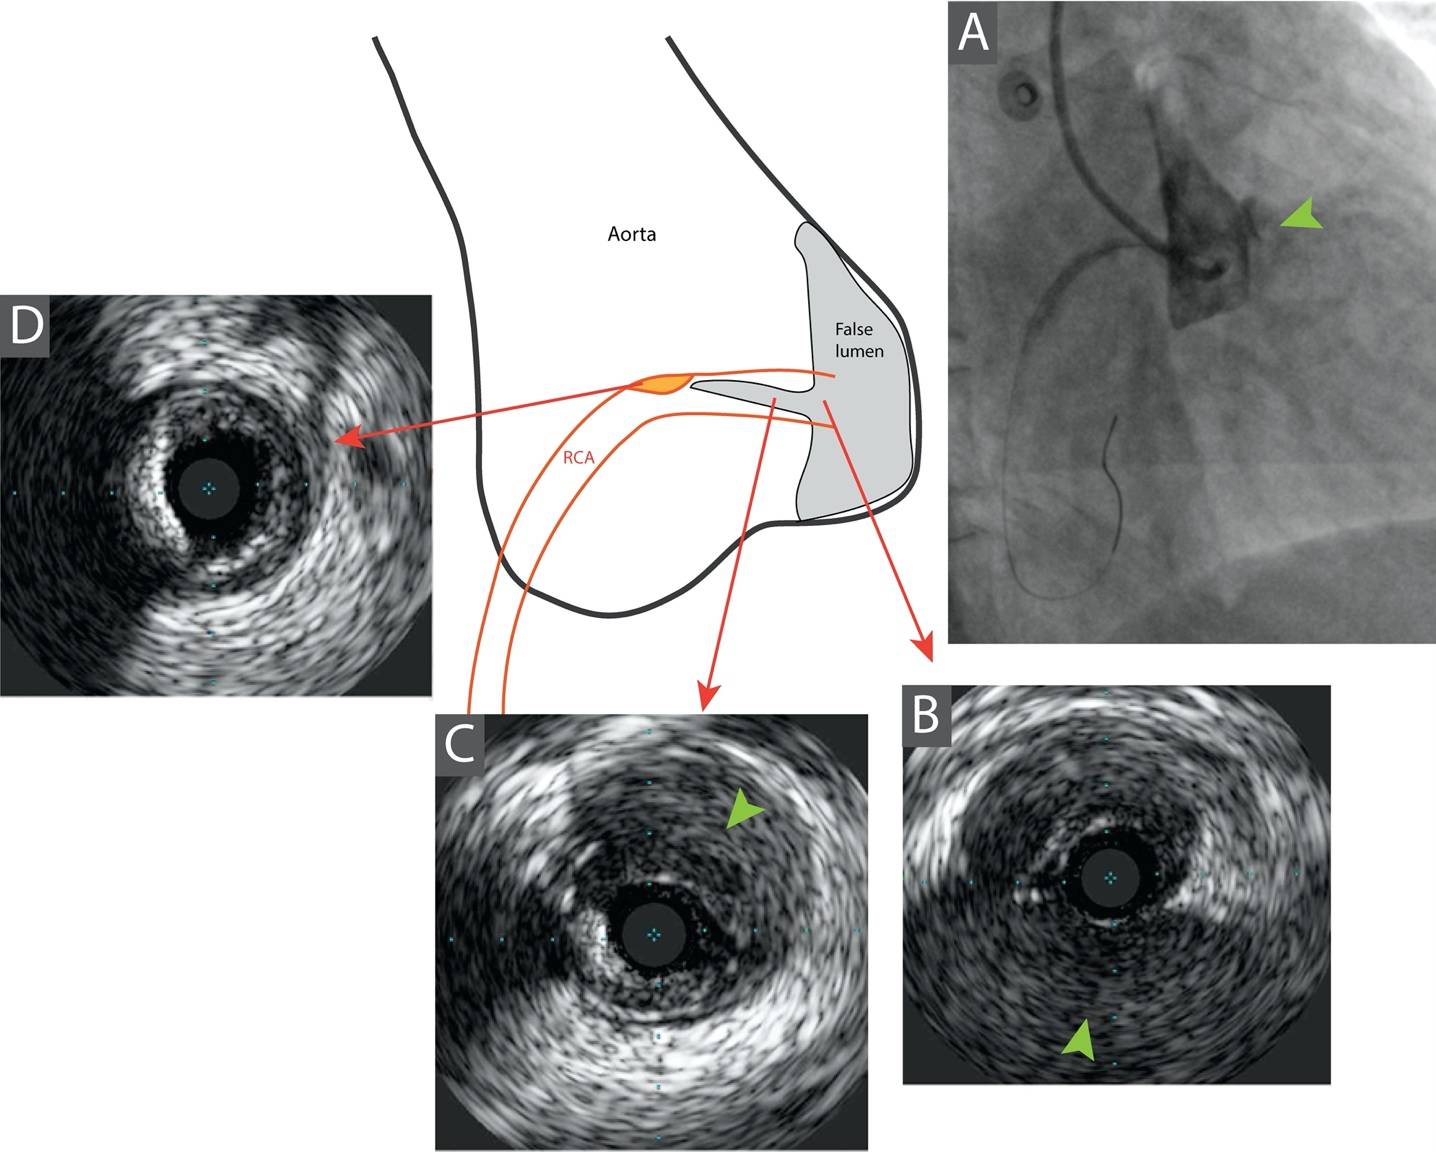

On-table-focused echocardiogram showed a dilated aortic root with moderate aortic regurgitation, which raised suspicion of an aortic dissection. Six-French right radial access was obtained and the left coronary system was engaged with an IL-3.5 guide catheter, which was unremarkable. The right coronary artery (RCA) was engaged with some difficulty. Coronary angiogram demonstrated an anteriorly located dissection flap over the right coronary cusp with extension of the hematoma into the proximal RCA resulting in Thrombolysis in Myocardial Infarction (TIMI)-2 flow (Figure 2A, Videos 1 and 2). Intravascular ultrasound (IVUS) (Volcano, Philips) demonstrated the presence of a hematoma extending from the ostial to the proximal RCA, with its propagation probably hindered by a pre-existing calcified plaque at the proximal RCA (Figure 2B-D, Video 3). The coronary flow remained sluggish after serial balloon dilatation. In view of ongoing ischemic symptoms with persistent ST-segment elevation and after discussion with the on-site cardiothoracic surgeons at our hospital, our team decided to proceed with stenting to the RCA. A 3.5 x 24-mm drug-eluting stent was implanted at the proximal RCA, and ST elevation improved post-stenting. Final angiogram showed satisfactory flow to the RCA (Figure 3).